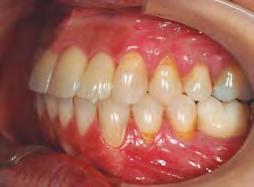

–Corticotomías y Ortodoncia. Ampliando límites del movimiento dental, por la Dra. Aranzazu Senosiain y cols. [50]

–Tratamiento de un caso de Ortodoncia y Cirugía Ortognática con placas preformadas y tecnología 3D, por la Dra. Elena Bonilla Morente y cols. [62]

–Uso del anclaje esqueletal como alternativa eficiente en el manejo ortopédico de clases III por deficiencia de maxilar superior, por el Dr. Carlos Becerra y cols. [74]

–MARPE, una alternativa a la disyunción en el paciente adulto, por el Dr. Enrique Solano y cols. [88]

Ortodoncia interdisciplinar, un enfoque colaborativo para el tratamiento integral de maloclusiones